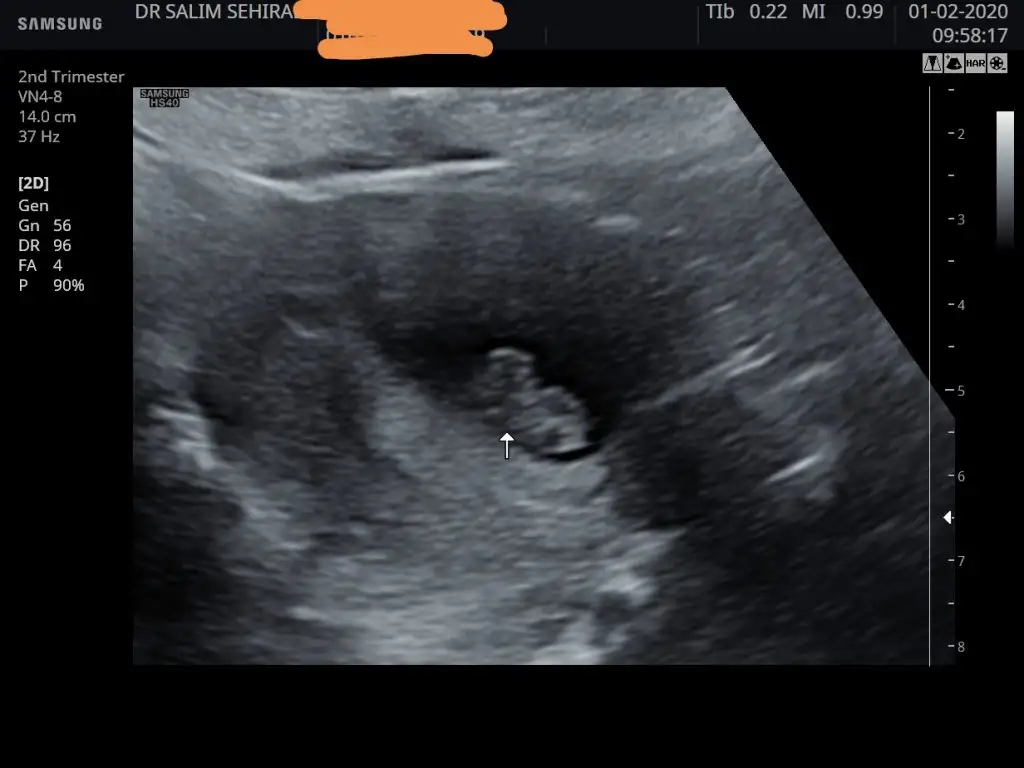

Ya bizim dr ultrason çıktısı veremiyor flaşa yüklüyoruz kağıdımı bitmiş ne bu nedenle çok üzülüyorum geçen haftanın görüntüsünü heyecandan istemeyi unuttum 8 haftalık hali nerde durduğunu ben anlamdım sizce nerde duruyor🙄ortada gibi ama